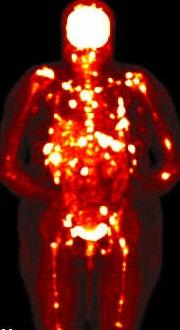

Myeloma Bone Disease

Myeloma in hand

Myeloma in the orbit

MRI (with contrast or STR images) very useful to delineate problems

MRI and FDG-PET in Multiple Myeloma

• > 3 focal lesions or SUV > 4.2 at diagnosis results in shorter PFS and OS[1]

• 65% of pts PET/CT negative 3 mos after ASCT with longer PFS and OS vs PET positive[1]

• Complete FDG suppression associated with durable disease control and prolonged OS[1]

• Skeletal survey recommended in cases of plasmacytoma, extramedullary disease, suspected spinal cord compression as well as with new symptoms or progression[2]

• MRI and/or PET/CT indicated when symptomatic areas show no abnormality on radiograph[3]

1. Zamagni E, et al. Blood. 2011;118:5989-5995. 2. Ludwig H, et al. Leukemia. 2014;28:981-992. 3. NCCN. Clinical practice guidelines in oncology: multiple myeloma. v.2.2014. 4. Boot M, et al. Novel prognostic modalities in multiple myeloma. 2013. MRI FDG PET Imaging Techniques[4]